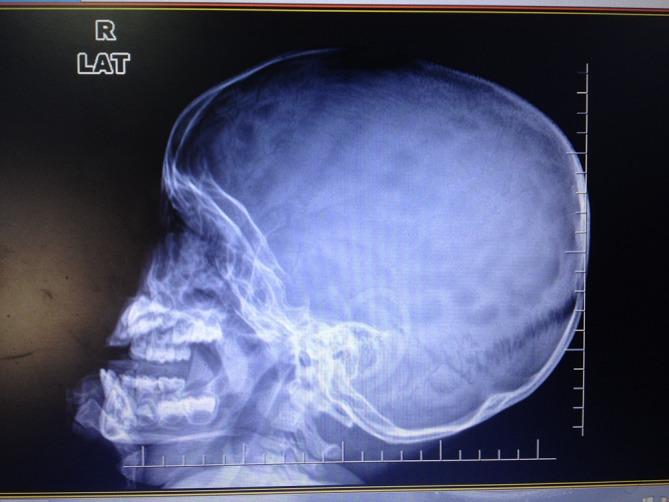

In recent years, most of the focus on improving the quality of paediatric care in low-income countries has been on improving primary care using the Integrated Management of Childhood Illness, and improving triage and emergency treatment in hospitals aimed at reducing deaths in the first 24 hours. There has been little attention paid to improving the quality of care for children with chronic or complex diseases. Children with complicated forms of tuberculosis (TB), including central nervous system and chronic pulmonary TB, provide examples of acute and chronic multisystem paediatric illnesses that commonly present to district-level and second-level referral hospitals in low-income countries. The care of these children requires a holistic clinical and continuous quality improvement approach. This includes timely decisions on the commencement of treatment often when diagnoses are not certain, identification and management of acute respiratory, neurological and nutritional complications, identification and treatment of comorbidities, supportive care, systematic monitoring of treatment and progress, rehabilitation, psychological support, ensuring adherence, and safe transition to community care. New diagnostics and imaging can assist this, but meticulous attention to clinical detail at the bedside and having a clear plan for all aspects of care that is communicated well to staff and families are essential for good outcomes. The care is multidimensional: biomedical, rehabilitative, social and economic, and multidisciplinary: medical, nursing and allied health. In the era of the Sustainable Development Goals, approaches to these dimensions of healthcare are needed within the reach of the poorest people who access district hospitals in low-income countries.

近年来,低收入国家提高儿科护理质量的工作重点大多放在通过儿童疾病综合管理改善初级护理,以及改善医院的分诊和急诊治疗以降低首24小时内的死亡率。对于改善慢性或复杂疾病患儿的护理质量,关注甚少。患有复杂形式结核病(包括中枢神经系统结核病和慢性肺结核)的儿童,是低收入国家地区级和二级转诊医院常见的急性和慢性多系统儿科疾病的例子。对这些儿童的护理需要全面的临床和持续质量改进方法。这包括在诊断往往不确定时及时决定开始治疗,识别和管理急性呼吸、神经和营养并发症,识别和治疗合并症,提供支持性护理,系统监测治疗和进展情况,进行康复治疗、心理支持,确保依从性,以及安全过渡到社区护理。新的诊断方法和成像技术可以提供帮助,但在床边细致关注临床细节,并为护理的各个方面制定清晰的计划并与工作人员和家庭进行良好沟通,对于取得良好结果至关重要。护理是多维度的:生物医学、康复、社会和经济方面;也是多学科的:医疗、护理和相关健康领域。在可持续发展目标的时代,低收入国家中前往地区医院就诊的最贫困人口需要能够获得针对医疗保健这些维度的方法。